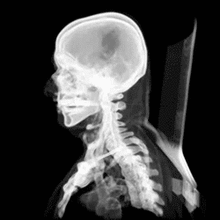

A CT scan makes use of computer-processed combinations of many X-ray images taken from different angles to produce cross-sectional (tomographic) images (virtual "slices") of specific areas of a scanned object, allowing the user to see inside the object without cutting.

Digital geometry processing is used to generate a three-dimensional image of the inside of the object from a large series of two-dimensional radiographic images taken around a single axis of rotation.[2] Medical imaging is the most common application of X-ray CT. Its cross-sectional images are used for diagnostic and therapeutic purposes in various medical disciplines.[3] The rest of this article discusses medical-imaging X-ray CT; industrial applications of X-ray CT are discussed at industrial computed tomography scanning.

CT produces a volume of data that can be manipulated in order to demonstrate various bodily structures based on their ability to block the X-ray beam. Although, historically, the images generated were in the axial or transverse plane, perpendicular to the long axis of the body, modern scanners allow this volume of data to be reformatted in various planes or even as volumetric (3D) representations of structures. Although most common in medicine, CT is also used in other fields, such as nondestructive materials testing. Another example is archaeological uses such as imaging the contents of sarcophagi. Individuals responsible for performing CT exams are called radiographers or radiologic technologists.[4][5]